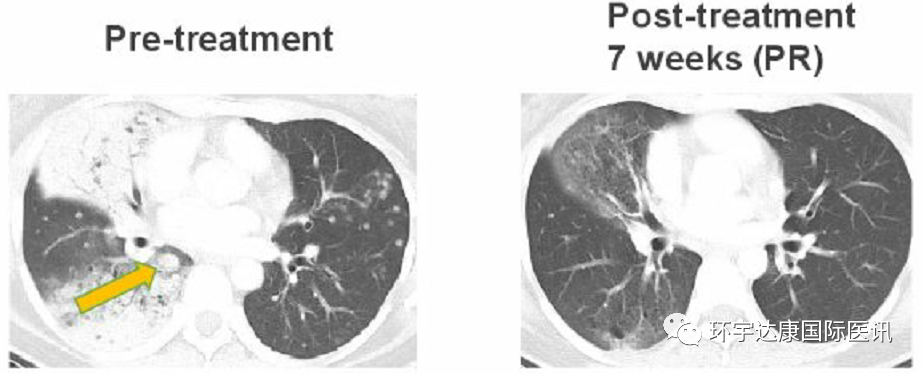

一位38岁的女士接受Taletrectinib治疗,在第7周时,肺部肿瘤迅速缩小,评效为部分缓解(PR),目前该患者仍在接受治疗中